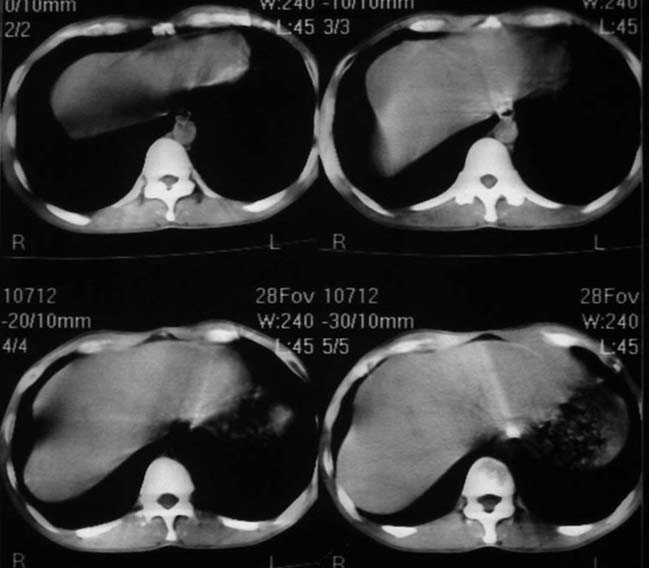

男,50y,右上腹包块痛10天,查:右上腹饱满,右肋下触及6*6cm大小包块,质硬,压痛。患者诉:10天前感冒胸闷,痛,后痛及右上腹部,既往有肝炎病史。

没有增强!只能考虑左叶内侧段巨块型肝癌(外生型)可能性大;胆囊呢?不除外胆囊癌累及肝脏。

我倒是先考虑胆囊癌(肿块型)肝脏受侵可能性大,做个c+

病变位于胆囊窝内,其内密度不均,肝总管及胆总管扩张,胃里面没有清水充盈,不解为什么楼主不做好了准备再做呢,支持:“左叶内侧段巨块型肝癌(外生型)可能性大;不除外胆囊癌累及肝脏”建议增强吧。

考虑:肝左内叶巨块型癌,主动脉旁淋巴结转移.(有一层面似见胆囊受压.)